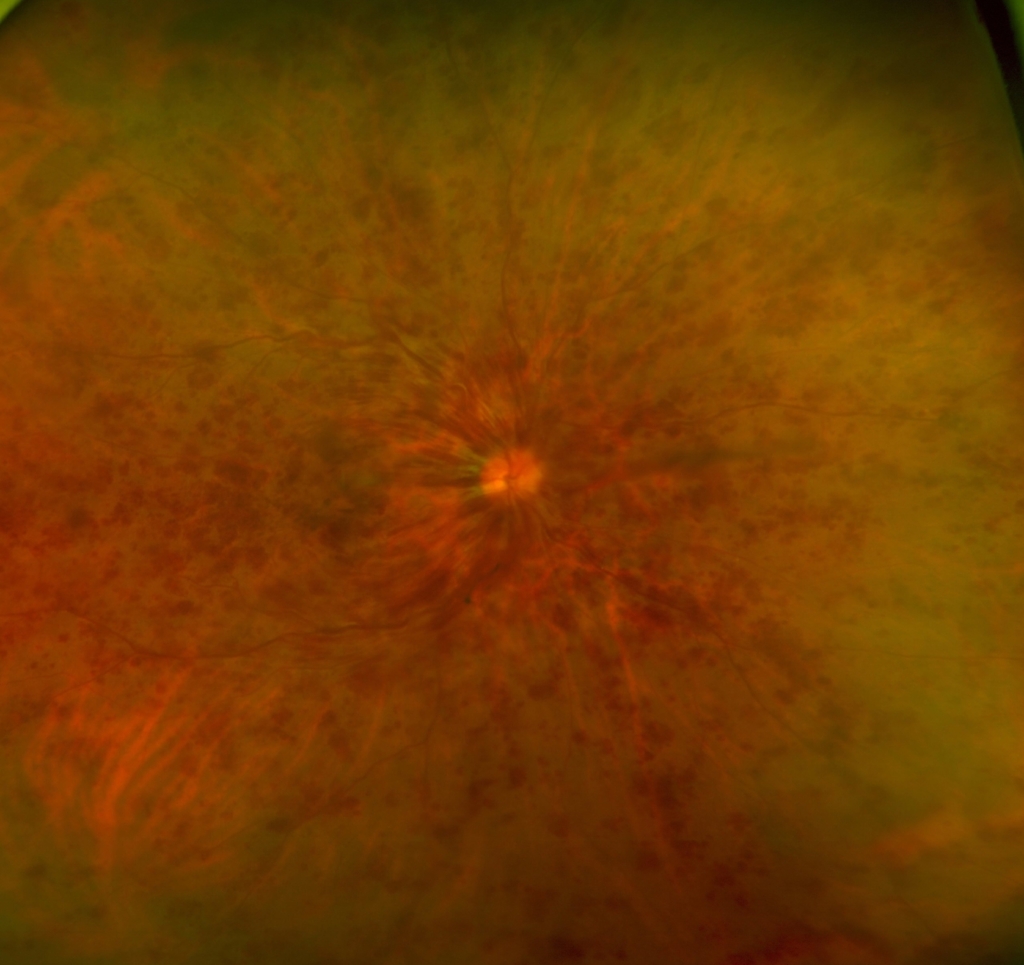

約4か月 抗VGEF(ラニビズマブ)の硝子体注射4回施行後、黄斑浮腫は注射直後に一時的に改善するが、4wで黄斑浮腫は著明に再発する。

アフリベルセプトに変更し、PRP施行。

発症後約6か月後